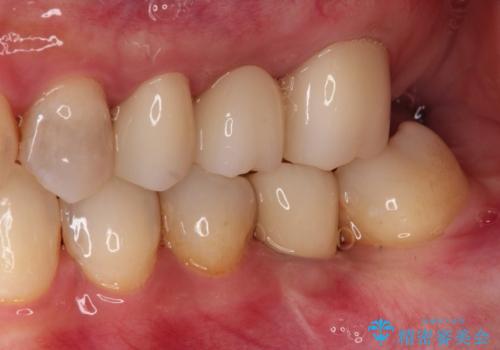

- 歯医者が怖くて悪い歯をそのままにしてしまった、悪いところを治したいとのことで来院されました。

虫歯の歯や、歯を抜いてしまったところをそのまま放置していたことにより、歯並びも悪くなっていました。

矯正をはじめ、根の治療・インプラント・セラミックによる全体治療を提案させていただき、治療をしていくこととなりました。